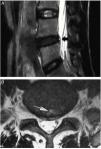

The study of degenerative pathology of the intervertebral disc (IVD) with magnetic resonance imaging (MRI) has generated such an extensive and ambiguous terminology that it causes confusion. The loss of the nucleus pulposus signal intensity (ISNP) in the T2 sequence of MRI, secondary to the early decrease in water content, is generally described as “black disc”, a term spread as a synonym for degenerative disc disease. On the other hand, to designate a supposedly symptomatic dehydrated disc, the following names have been introduced: “painful black disc”, “black disc syndrome” and “black disc disease”. In this way, the physiological dehydration of the NP present in the entire population from the third decade on, is arbitrarily considered a presumed radiological marker of discogenic back pain, with the consequent risk of being the target of unnecessary interventions. Dehydrated discs suspected of being a source of pain present, in addition to the decrease in ISNP, other radiological signs such as a high intensity zone (HIZ) in the posterior part of the annulus fibrosus (AF), protrusion, loss of height or Modic changes.